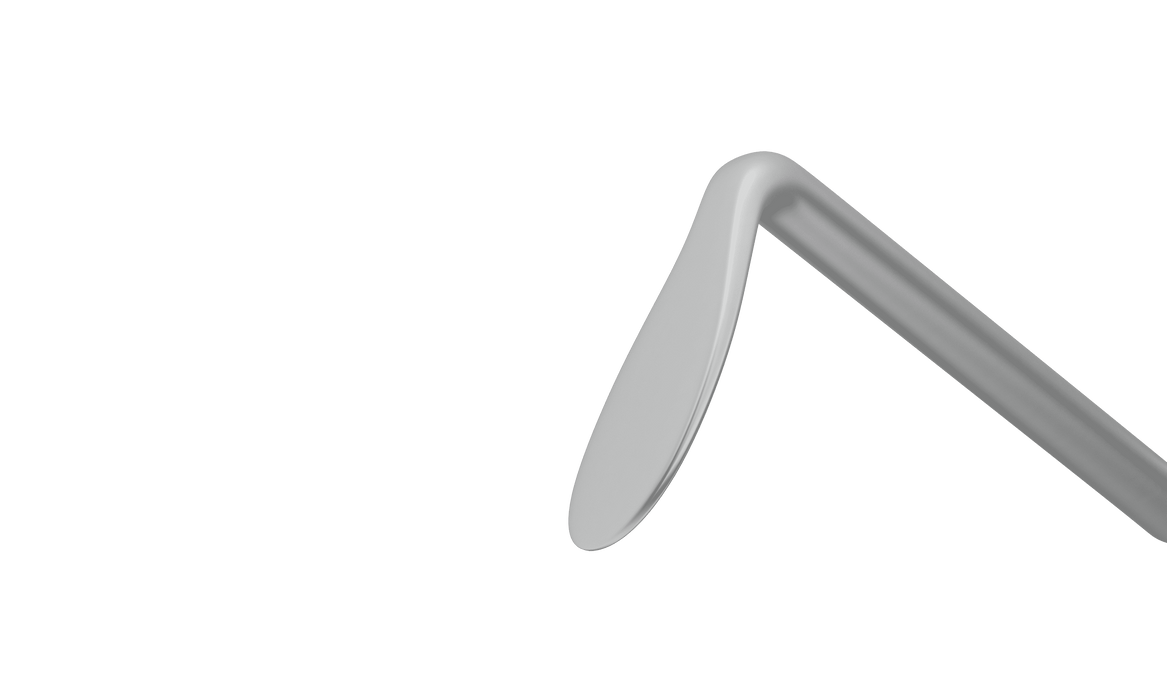

7-128 Quick Chopper with Rounded Edge, RHD, Round Handle, Length 120 mm, Round Titanium Handle —

Rounded edge is safe for the posterior capsule., RHD - a model is designed for a Right Hand Dominant Doctor, the chopper is to be held in the

Ball-shaped tip for efficient capsule protection. Quick safety chopper with rounded edge reduces pressure when it comes to capsule. Adaptable to

114R 7-1361 Seibel Chopper/Quick Chopper with Rounded Edge, RHD, Length 138 mm, Round Titanium Handle

7-1281 Quick Chopper with Rounded Edge, LHD, Length 120 mm, Round Titanium Handle —

Quick Chopper with Rounded Edge - 7-128 - accuspire

7-128 Quick Chopper with Rounded Edge, RHD, Round Handle, Length 120 mm, Round Titanium Handle —

7-128 Quick Chopper with Rounded Edge, RHD, Round Handle, Length 120 mm, Round Titanium Handle —

Rounded edge is safe for the posterior capsule., RHD - a model is designed for a Right Hand Dominant Doctor, the chopper is to be held in the

206R 7-128 Quick Chopper with Rounded Edge, RHD, Round Handle, Length 120 mm, Round Titanium Handle